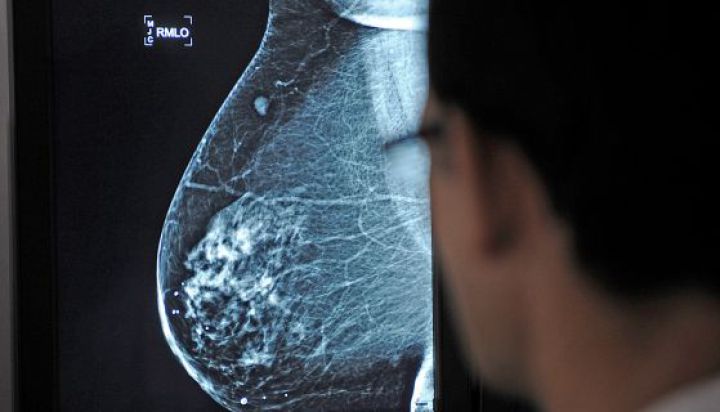

Cambio de tercio en la cirugía reparadora de mama. Tras 20 años ensalzando las bonanzas de la cirugía conservadora —esto es, extirpar lo mínimo imprescindible para neutralizar el tumor y preservar lo máximo posible el propio pecho—, los cirujanos plásticos han dado una vuelta de tuerca a las guías clínicas y han reivindicado la mastectomía (extirpación total de la mama) y la reconstrucción inmediata como una alternativa en alza. Los resultados de la cirugía conservadora no son los esperados, a ojos de los cirujanos plásticos, según estos especialistas, que esta semana se han reunido en un congreso internacional en el hospital Sant Pau de Barcelona, alrededor del 40% de las cirugías conservadoras no obtienen los resultados esperados y condicionan la calidad de vida de las pacientes. A la larga, muchas mujeres sometidas a esta técnica acaban pasando de nuevo por el quirófano para hacerse una mastectomía y una reconstrucción inmediata.

La buena imagen que se labró la cirugía conservadora, convertida incluso en un indicador de calidad, la postuló como la práctica más empleada tras el proceso quirúrgico en un cáncer de mama. Preservar la forma del pecho es una prioridad desde hace más de 20 años y actualmente, hasta el 70% de las intervenciones de pecho optan por esta técnica. Los oncólogos la defienden pero los cirujanos plásticos han abierto la puerta a evaluar el impacto y el resultado a largo plazo de estas técnicas. "Hay que mirar cuál es la calidad de vida de este 70% que se somete a la cirugía conservadora. Un estudio realizado en Francia demuestra que entre al 30% o al 40% de estas mujeres les aporta unos resultados pobres porque a la larga provoca una asimetría de forma y tacto que condiciona la vida de la paciente", apunta el doctor Jaume Masià, director del Servicio de cirugía plástica de Sant Pau y anfitrión del evento.